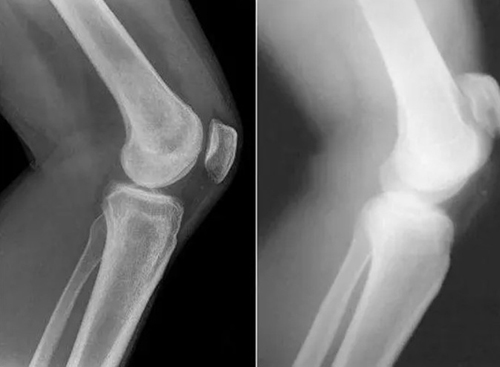

สาเหตุหลักของโรคข้อ คือการตกตะกอนของผลึกเกลือในข้อ เนื่องจากระบบไหลเวียนโลหิตและของเหลวไขข้อ (synovial fluid) เสื่อมลง:

- กรดยูริก (Urate crystals) ทำให้เกิดโรคเกาต์

- แคลเซียมเกาะกระดูก (Osteophytes) คือตัวการของโรคข้อและกระดูกกว่า 97% เช่น โรคข้ออักเสบ โรคข้อเสื่อม โรคกระดูกอ่อน โรคกระดูกพรุน โรคไขข้ออักเสบ โรคถุงน้ำในข้ออักเสบ และแม้แต่ซีสต์ของปมประสาท

เมื่อเกลือเหล่านี้เกาะอยู่บนพื้นผิวของข้อต่อ คราบเกลือเหล่านี้เหมือนกระดาษทรายที่ทำลายเนื้อเยื่อรอบโดยรอบ กระดูก และกระดูกอ่อน เมื่อผลึกโตขึ้น เกลือจะเริ่มทำลายเนื้อเยื่อของกล้ามเนื้อ เอ็น หลอดเลือด และเส้นเลือดฝอย ทำให้เกิดการอักเสบ ติดเชื้อ บวม ก่อให้เกิดการอักเสบและปวดอย่างรุนแรง

ในกรณีรุนแรง การสะสมเกลือจำนวนมากอาจทำให้กระดูกหักได้ง่ายเมื่อมีการเคลื่อนไหวอย่างกะทันหัน ส่งผลให้พิการและข้อต่อไม่สามารถเคลื่อนไหวได้